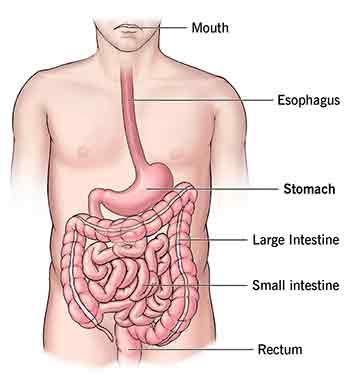

A case which illustrates a typical history is one of a young man in his late thirties who had been suffering from a persistent pain in his mid-ribcage on the right for many years. He worked at a computer for long hours every day. He had scans and had been to many doctors, massagists, Osteopaths and Chiropractors in search of an answer to his pain.

I found hypertonus in the muscles in the area of pain. His overall structure was slightly asymmetrical. He also suffered from an intermittent pain in his left front ribcage. Both this and the mid-back pain in his perception seemed to be aggravated by his digestive problems.

I gave him treatment to all the afflicted areas including the stomach and the pain disappeared. Some follow up sessions have maintained this marked improvement.

The abdomen is frequently under a lot of pressure (intra-abdominal pressure). This can be the result of sluggish digestion or vice-versa. Many digestive and bowel problems can be significantly relieved using techniques which can reduce such pressure, abdominal massage being one of them. The intestines can become blocked and kinked, they can have areas which produce colic and discomfort. The abdomen holds a lot of emotional tension which can feed back and affect the behavior of the individual, ranging from increased anxiety to altered mental states if the 'Biome' is affected by bacterial overgrowth.